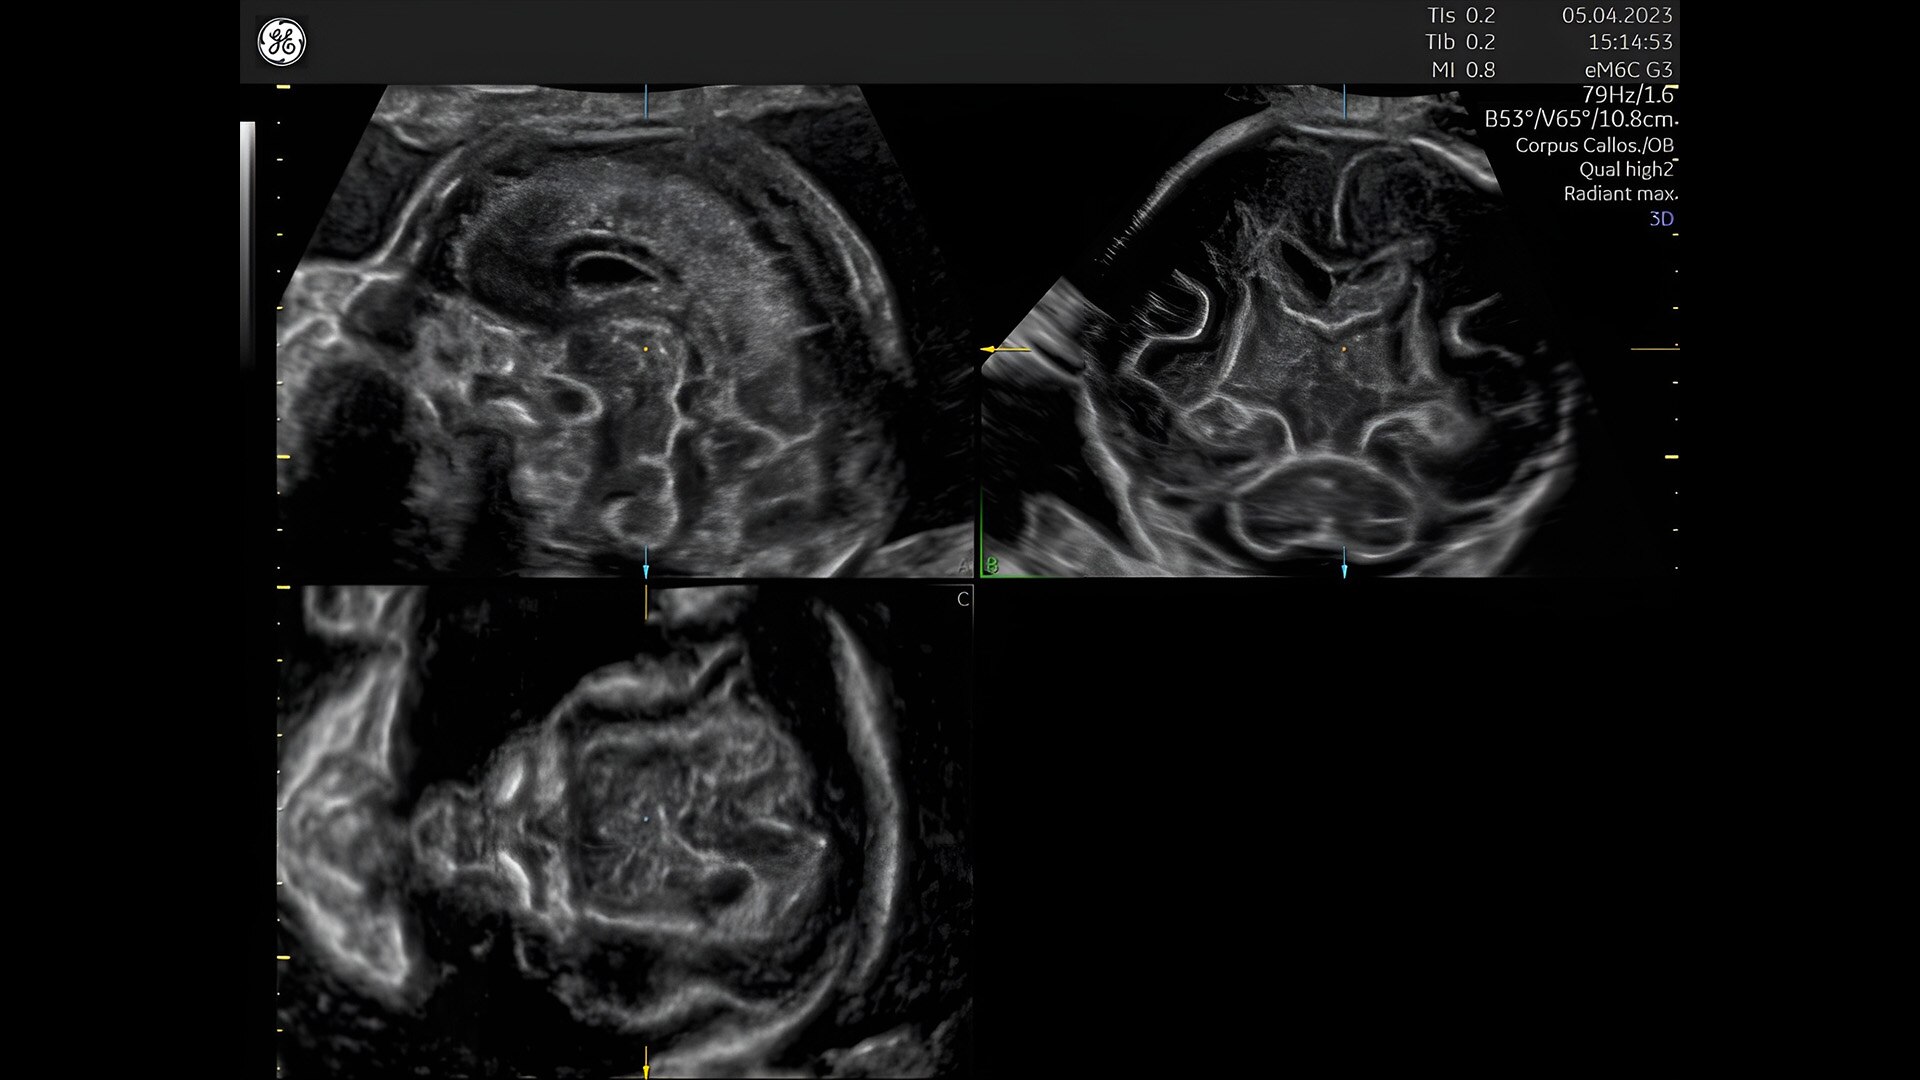

First trimester exams

Perform detailed exams with high-resolution for early insights to fetal health

Fetal heart assessment

Detect, diagnose, and monitor with confidence using Radiant and fetalHQ

Fetal heart evaluation

Get to the heart of the matter

Identifying fetal cardiac abnormalities earlier means you can intervene sooner, plan for delivery, and potentially improve outcomes. The Voluson Expert 22 provides a full solution of progressive tools, to help distinguish the tiniest structures with stunning clarity to provide patient answers faster.